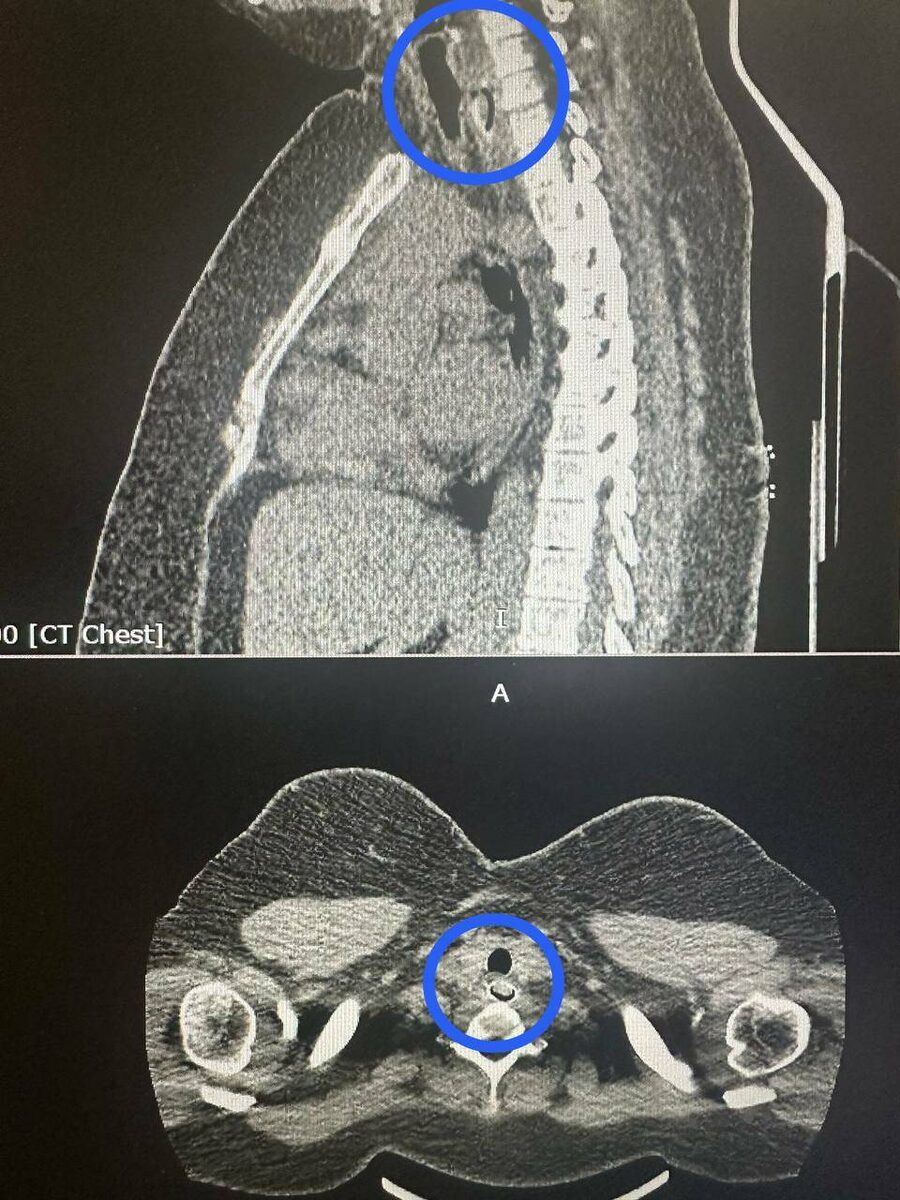

Компьютерная томография показала, что косточка перекрыла почти весь просвет пищевода. Достать ее через рот было невозможно. Поэтому хирурги сделали разрез в области шеи и пищевода, чтобы аккуратно убрать инородное тело.

«Такие ситуации опасны осложнениями из-за повреждений органов средостения. В таких случаях может развиться воспаление вплоть до гибели пациента», – отметили в пресс-службе РКБ.